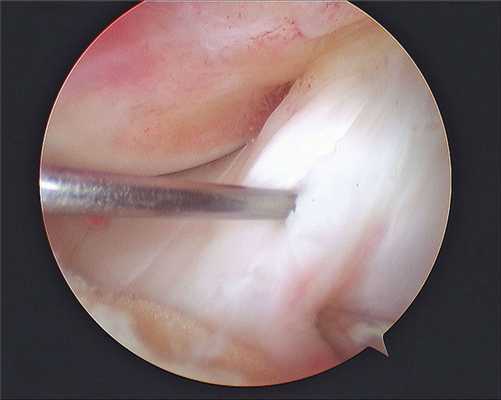

- Артроскопия. Инвазивный метод диагностики, который чаще всего используют при свежем посттравматическом артрите. Артроскопия позволяет осмотреть суставную полость изнутри и, при необходимости, выполнить в ней несложные манипуляции (эвакуировать скопившуюся кровь, удалить фрагменты разорванного мениска, сшить поврежденную связку).

Изображение полости сустава.

В целях высокоинформативной диагностики специалист через микропортал вводит рабочую трубку устройства внутрь сустава, в которую вмонтированы система ультрасильных линз, мощный световой источник и видеозаписывающая цифровая техника. Все структуры, что «видит» артроскоп, визуализируются на экране в «живом» виде, причем изображение поступает в многократно увеличенном формате. Врач может найти точное расположение травмы или дегенеративных изменений, установить характер патологии, степень тяжести и принять меры.

Метод используется не только как средство диагностики, но и в качестве лечебно-восстановительной тактики. Обнаружив те или иные нарушения хрящевой поверхности, доктор может сразу же их ликвидировать. Оперативные манипуляции он выполнит через дополнительный разрез (размер около 6 мм) с использованием микрохирургических инструментов, при этом весь процесс он будет совершать, глядя на монитор.

Операционное поле, можно видеть свечение внутри.

Видео в реальном времени транслируется на экране, выявляет любые существующие дефекты в больном сочленении. Если врач посчитает нужным выполнить регенерацию патологических элементов, он создаст дополнительный разрез (6-8 мм), через который нужным инструментом из микрохирургического набора устранит обнаруженный дефект. Он может сделать частичную резекцию костно-хрящевых тканей, пластику связок и сухожилий, сшивание или удаление (частичное, полное) мениска, экспроприировать хондромные тела, извлечь выпот и гной, ввести противовоспалительные лекарства, взять фрагмент тканей или синовии для изучения их состава и др.